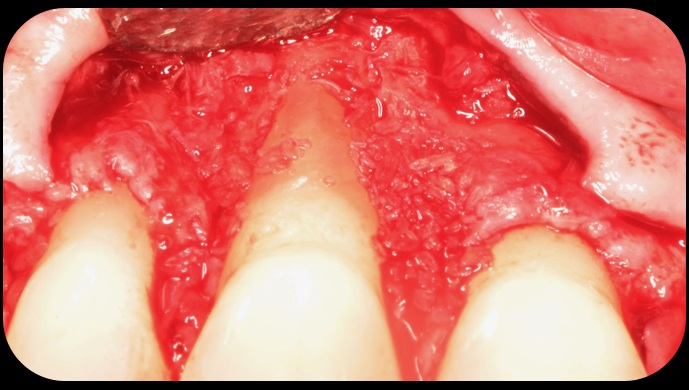

Preoperative recession.

Fig. 8

Acellular dermal graft combined with enamel matrix derivative.

Fig. 9

The 2.5-year postoperative photograph.

Fig. 10

In the coming decades, restorative treatment for aging patients who experience facial growth with recession and erosion below the cemento-enamel junction because of tooth movement may be especially challenging. However, if dentists can employ the tenets of regeneration using autogenous tissues or a cellular dermal matrix combined with enamel matrix derivatives as a regulatory protein, they may predictably achieve large amounts of root coverage with thickened periodontium. This would not eliminate the need for restorative dentistry, but would enable restorative dentists to place restorations that are supragingival and are easily accessible for the patient and the therapist during maintenance (Figure 8 through Figure 10).